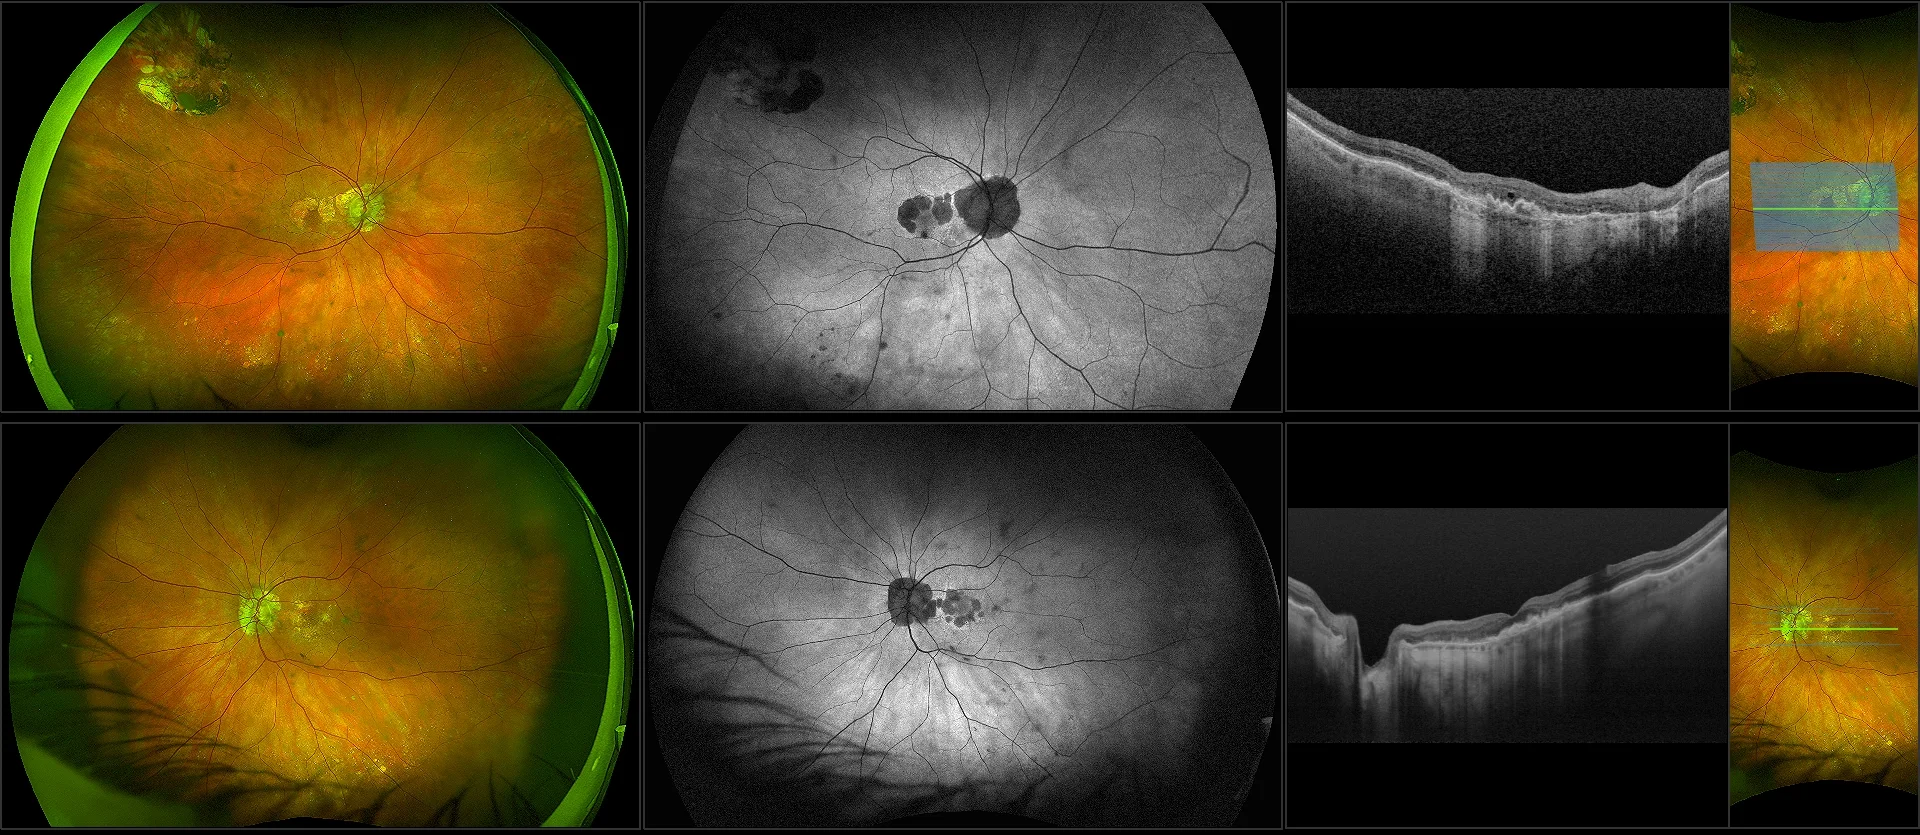

This material is designed as a searchable reference resource to support clinical decision-making. The information contained here should be used as general guidance when viewing optomap and OCT images from Optos devices. The differential diagnosis should be made under the direction of the responsible physician. These images were taken on the latest ultra-widefield optomap devices.

optomap Recognizing Pathology is searchable by pathology and/or optomap image modality. You may search by multiples of each selection. Each individual case is represented by the accompanying thumbnail image. Most cases include several different optomap image modalities. To view a full description of the case, please click on the thumbnail. Each image in the case will be made available through our OptosAdvance software which provides multi-dimensional visualization of digital images to aid in the analysis of anatomy and pathology. Support and pathology definitions can be found by selecting one of the buttons, above. Should you have questions, please complete the form below.